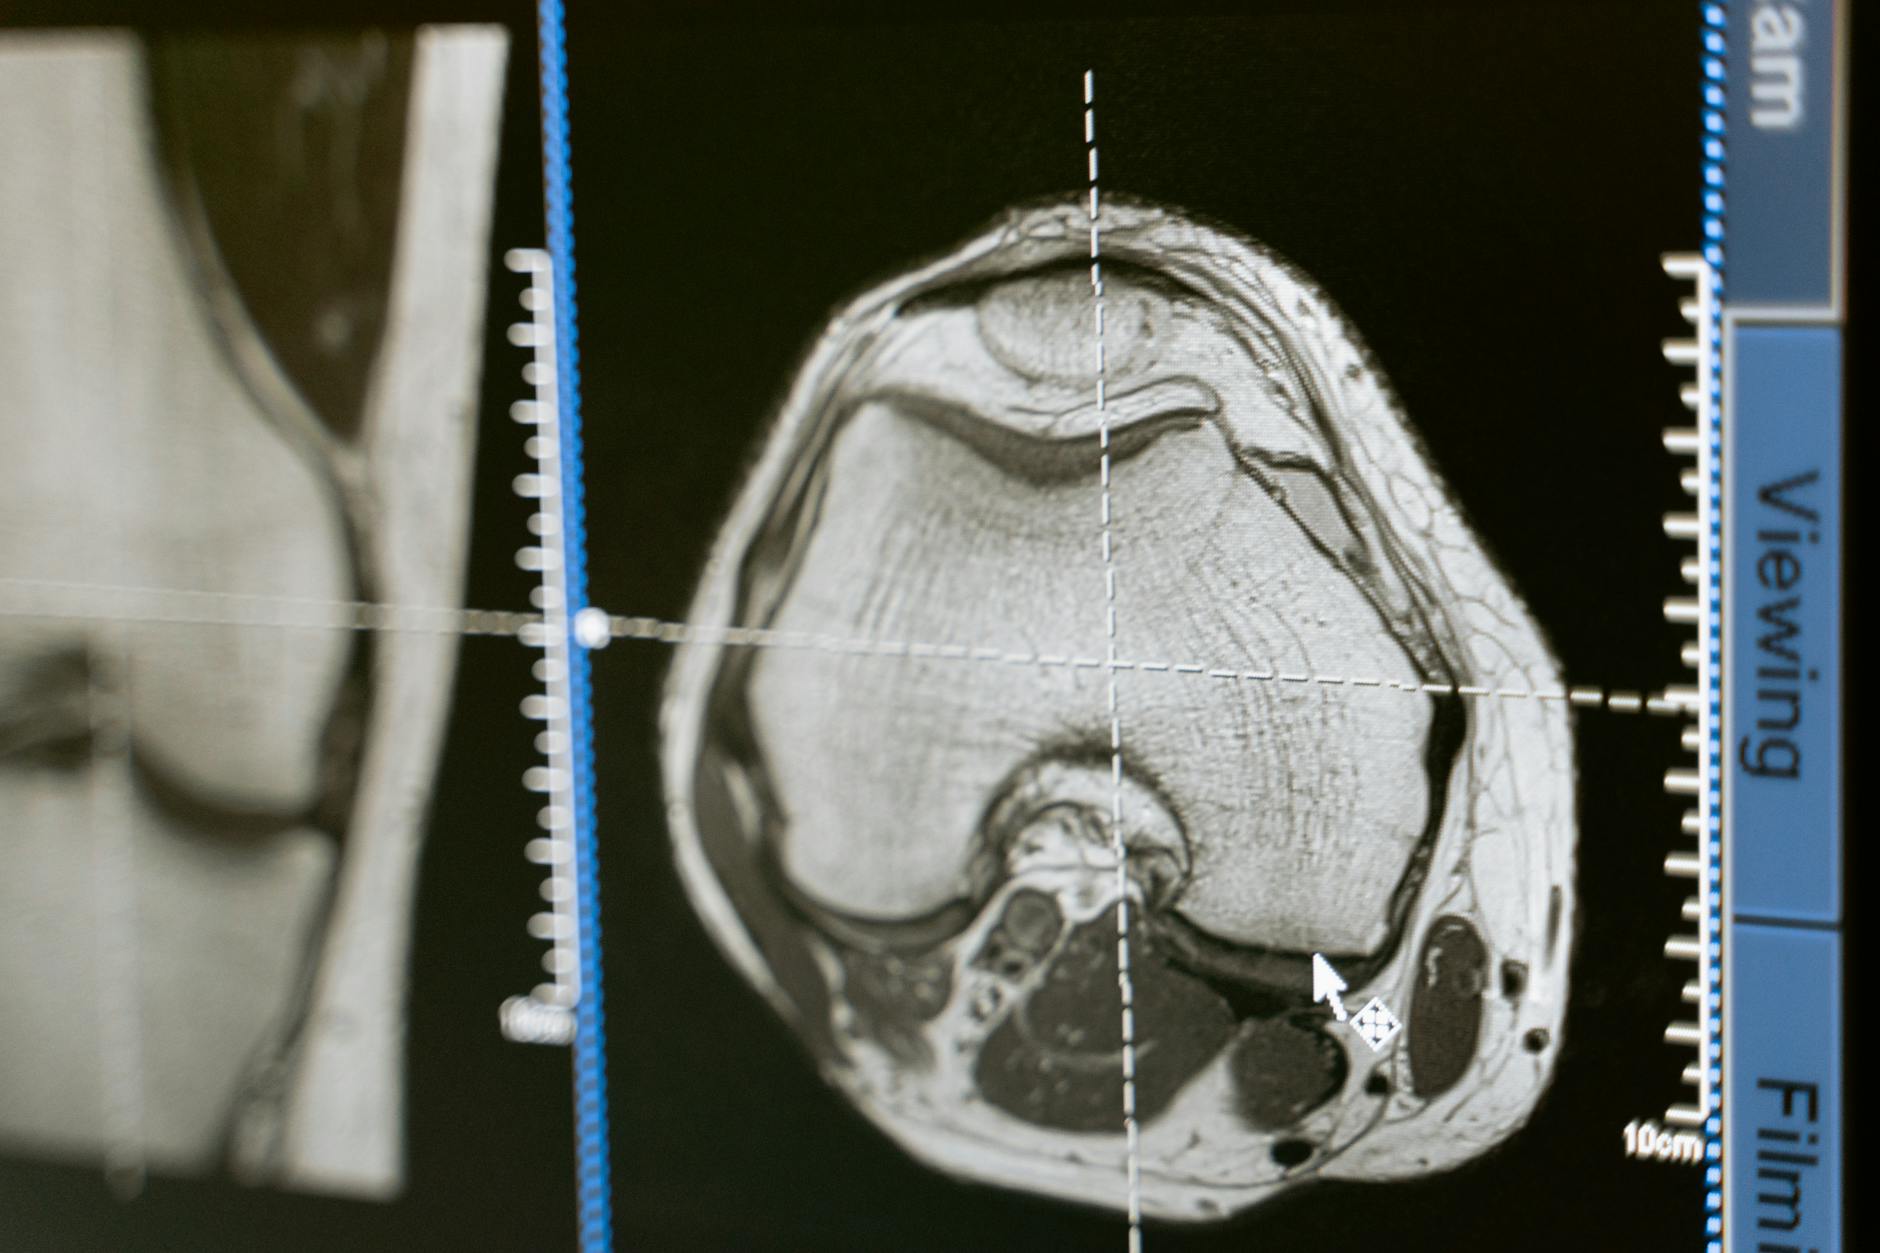

Gadolinium is a rare earth metal that, when bound to a chelating agent, is used intravenously to enhance the quality of MRI scans. The contrast agent helps radiologists see blood vessels, tumors, inflammation, and other abnormalities more clearly. Historically, GBCAs were considered safe because the gadolinium was supposed to be excreted from the body relatively quickly through the kidneys. However, research published over the past decade and a half has demonstrated that gadolinium can remain in the body long after the MRI is completed, depositing in brain tissue, bones, skin, and organs even in patients with normal kidney function. This discovery fundamentally challenged the safety profile that manufacturers had promoted for decades. Lawsuits have been filed because patients allege that manufacturers knew or should have known about the risks of gadolinium retention and failed to provide adequate warnings. The earliest wave of litigation focused on nephrogenic systemic fibrosis, a debilitating and sometimes fatal condition affecting patients with impaired kidney function.

Gadolinium is a rare earth metal used in contrast agents that are injected intravenously before certain MRI procedures. It enhances the visibility of internal structures, blood vessels, and abnormalities on MRI images by altering the magnetic properties of nearby water molecules. GBCAs have been widely used since the late 1980s and are administered in tens of millions of MRI procedures worldwide each year.